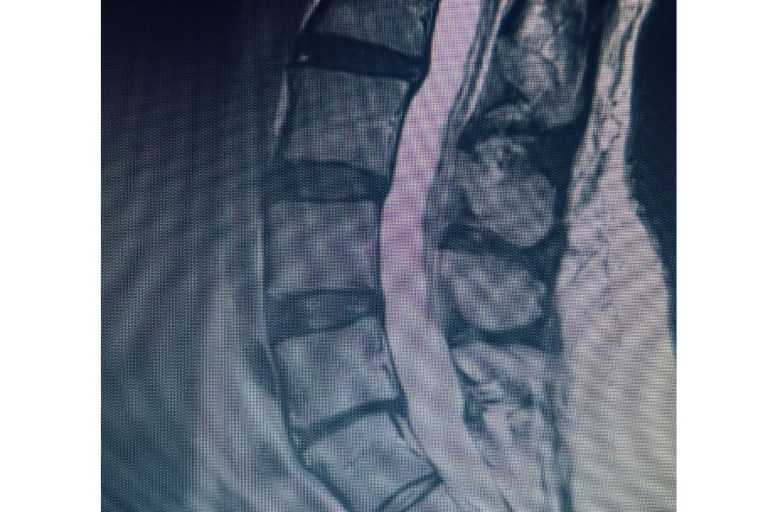

Cervical total disc replacement or disc arthroplasty is becoming an increasingly popular procedure. Now, the cervical disc replacements are even approved for doing 2 levels, as in this recent case that I performed. Is it right for you? Many things are possible in spine surgery but only a few things are most appropriate for you…